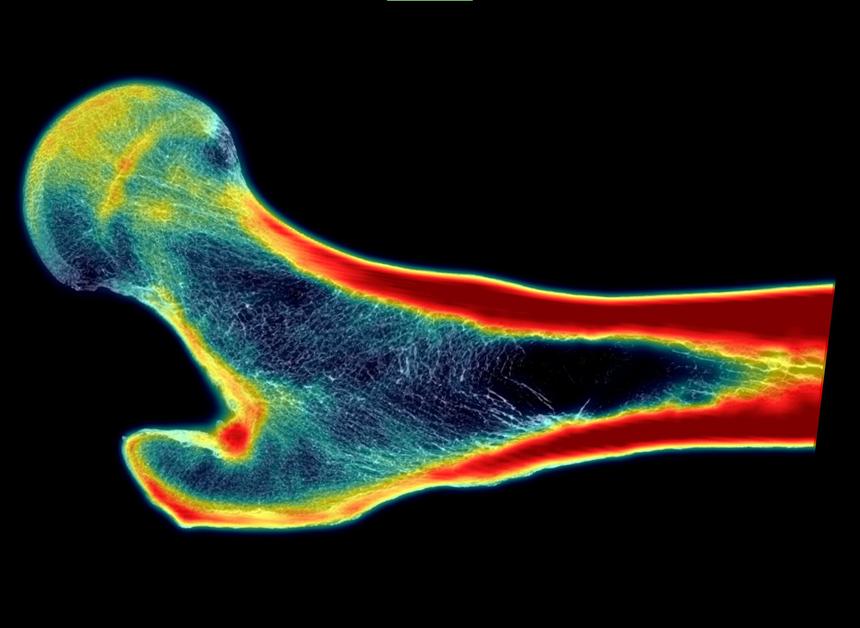

Ученые из Юго-западного исследовательского института (SwRI) разработали новую технологию, которая может значительно улучшить диагностику остеопороза и снизить риск переломов у пожилых людей. Метод основан на искусственном интеллекте (ИИ) и позволяет создавать изображения костей в высоком разрешении, которые детально показывают их внутреннюю структуру. Это помогает врачам точнее оценивать прочность костей и выявлять пациентов с высоким риском переломов.

В новом подходе используется глубинное обучение, которое обучает нейросеть восстанавливать высококачественные изображения из стандартных снимков. Это позволяет моделировать структуру кости и прогнозировать её прочность.